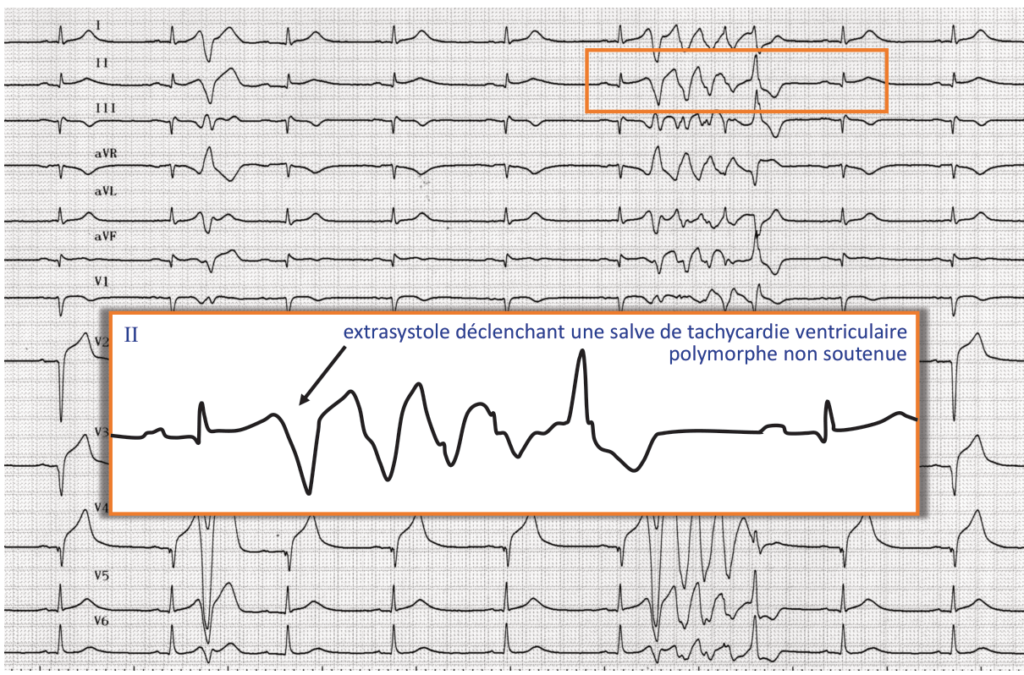

Morphologie identique de l’extrasystole ventriculaire; extrasystole déclenchant une salve de tachycardie ventriculaire polymorphe non soutenue;